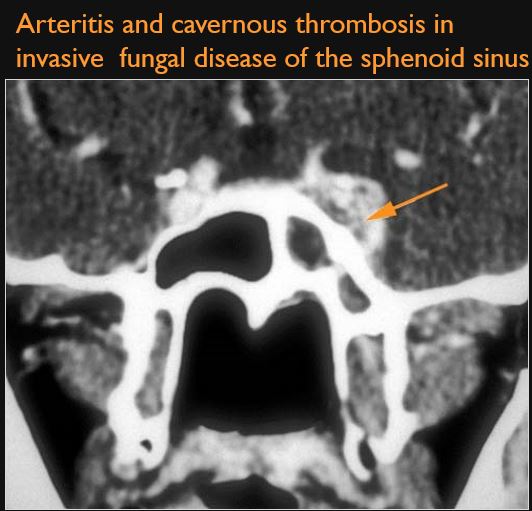

There is evidence of cavernous sinus thrombosis and/or inflammatory morphologic features in the cavernous sinus or para-cavernous region.

There is a compressive lesion or infiltrative process present in the cavernous sinus or para-cavernous area.